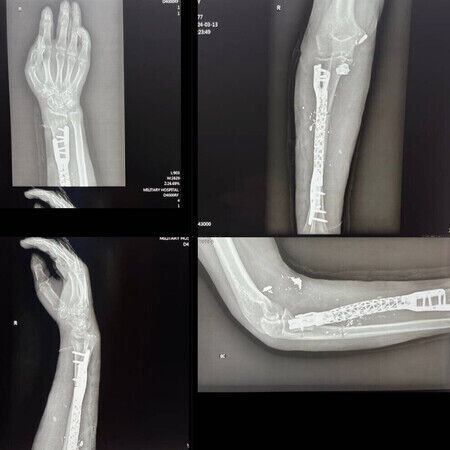

- Bei einer komplizierten Operation konnten Chirurgen einen Titan-Knochenkäfig als Ersatz für den zerstörten Unterarmknochen eines Soldaten einsetzen. Der Eingriff ermöglichte die Wiederherstellung der Stabilität und Funktion des Arms.